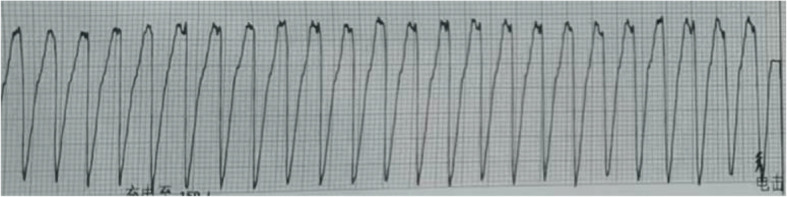

心电风暴(CES)是一种危及生命的电不稳定状态,其特征是24小时内发生3次或更多的持续性室性心律失常。星状神经节阻滞在心脏手术治疗中的应用很少有报道。在此,我们报告一位接受星状神经节阻滞后室性心律失常完全缓解的病人。我们报告一例35岁男性接受主动脉瓣置换术。有主动脉瓣狭窄的患者计划进行主动脉瓣置换术和三尖瓣成形术。停止镇静后,恶性心律失常复发。我们对病人进行了星状神经节阻滞。结果,患者完全消除了症状,并在术后一年成功地恢复了正常的生产生活。对于心脏手术后对药物治疗无反应的室性心动过速患者,星状神经节阻滞是一种安全有效的治疗方法。

Cardiac electrical storm (CES) is a life-threatening state of electrical instability characterized by 3 or more episodes of sustained ventricular arrhythmia within 24 h. The application of stellate ganglion block for the treatment of cardiac surgery has rarely been reported. Herein, we report a patient whose ventricular arrhythmia was completely relieved after receiving a stellate ganglion block. We present a case of a 35-year-old male who underwent aortic valve replacement. The patient who had aortic valve stenosis was scheduled for aortic valve replacement and simultaneous tricuspid valvuloplasty. After sedation was discontinued, malignant arrhythmias recurred. We performed stellate ganglion block for patient. As aresult, the patient achieved a complete resolution of symptoms and successfully resumed a normal productive life one year post-surgery. Stellate ganglion block is a safe and effective treatment for patients with ventricular tachycardia unresponsive to drug therapy following cardiac surgery.